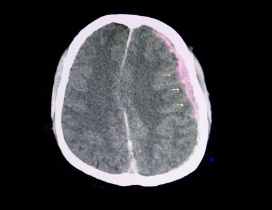

뇌출혈이 의심되는 경우, 즉시 의료 기관을 방문하여 정밀 진단을 받는 것이 중요합니다. 컴퓨터 단층촬영(CT)이나 자기공명영상(MRI) 검사를 통해 뇌 내부의 출혈 여부를 확인할 수 있으며, 필요한 경우 적절한 치료를 받을 수 있습니다.